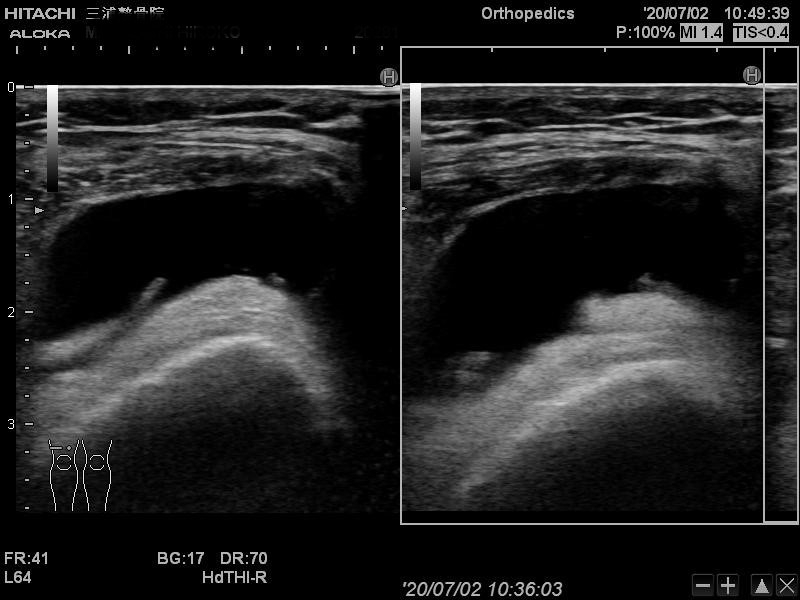

エコーの良い所として

動かしながらも観れるので

関節がどのくらいぐらついているかなども

判断できます。

こういった画像で状態や動きも参考にしながら